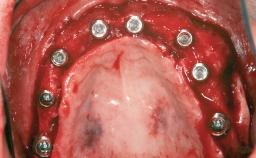

His main interests are in Computer Aided Maxillofacial and Implant Surgery, with a focus on Interdisciplinary Treatment, and in Orthognathic Surgery. He has many publications and lectures worldwide on digital tools, bone grafts, implants in the treatment of the esthetic area, complications, and the treatment of fully edentulous patients.

His main professional interests are in advanced and complex implant surgeries,

orthognathic surgery and digital technology.